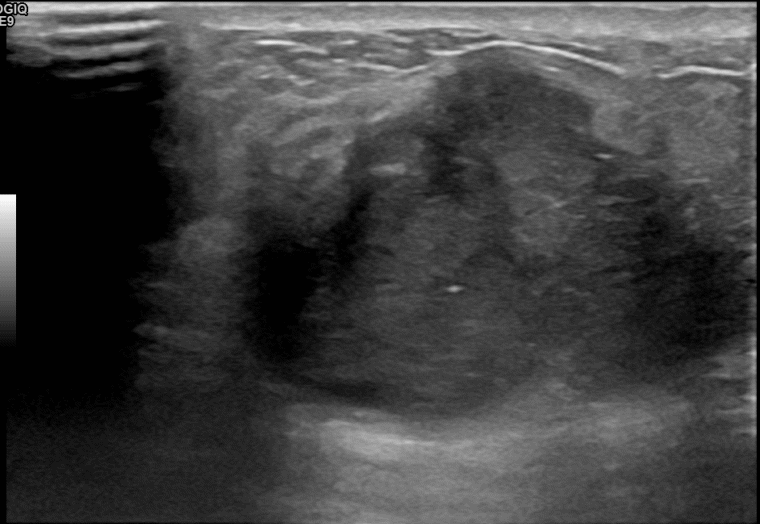

상기환자는 만져지는 멍울로 내원하신 60대초반

여성분으로 의심스러운 우측혹 조직검사 시행해 침윤성암으로 진단되었습니다